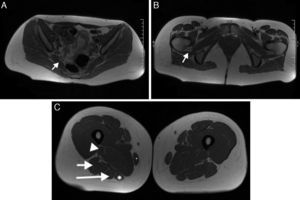

Niño de 4 años con marcha polineurítica de un año de evolución, con EMG compatible con lesión del nervio peroneo. A) Secuencia SPGR ponderada en T1 con saturación de la grasa e inyección de gadolinio. Muestra un nódulo en la división peronea del nervio ciático (flecha corta). Por detrás se observa la división tibial con un patrón fascicular normal (flecha larga). B) Reconstrucción MPR curva donde se observa el engrosamiento fusiforme en el tercio distal del nervio ciático (flecha).

El neurofibroma plexiforme tiene una apariencia patognomónica. Se observa como una nodularidad difusa de todo el recorrido del nervio y sus ramas, con una hiperintensidad similar al agua en las secuencias ponderadas en T2. Los de gran volumen reemplazan el tejido adiposo creando una apariencia en «panal». Clínicamente se manifiestan por elefantiasis neuromatosa37–39 (fig. 6).